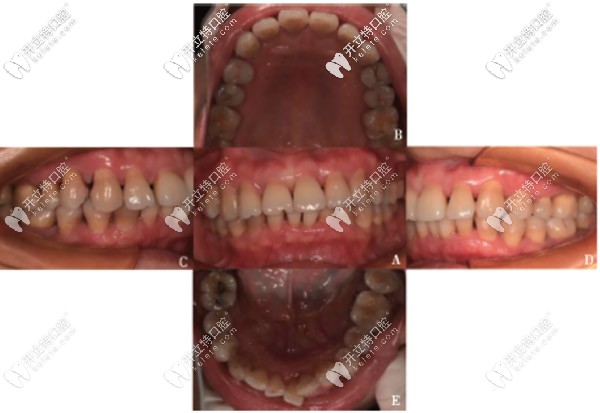

基礎(chǔ)治療后2年Florida檢查▲

經(jīng)過(guò)兩年的基礎(chǔ)治療后,復(fù)查時(shí)口內(nèi)顯示全口牙齦炎癥明顯減輕,牙齒松動(dòng)度明顯減輕,咬合關(guān)系有所改善,風(fēng)險(xiǎn)因素減少,評(píng)估為低風(fēng)險(xiǎn)。

PD≥5mm的位點(diǎn)數(shù)是疾病進(jìn)展的重要因素,顧客在治療前評(píng)估為高風(fēng)險(xiǎn),目前為低風(fēng)險(xiǎn)。同時(shí)還存在咬合創(chuàng)傷,也會(huì)加重牙周組織炎癥。